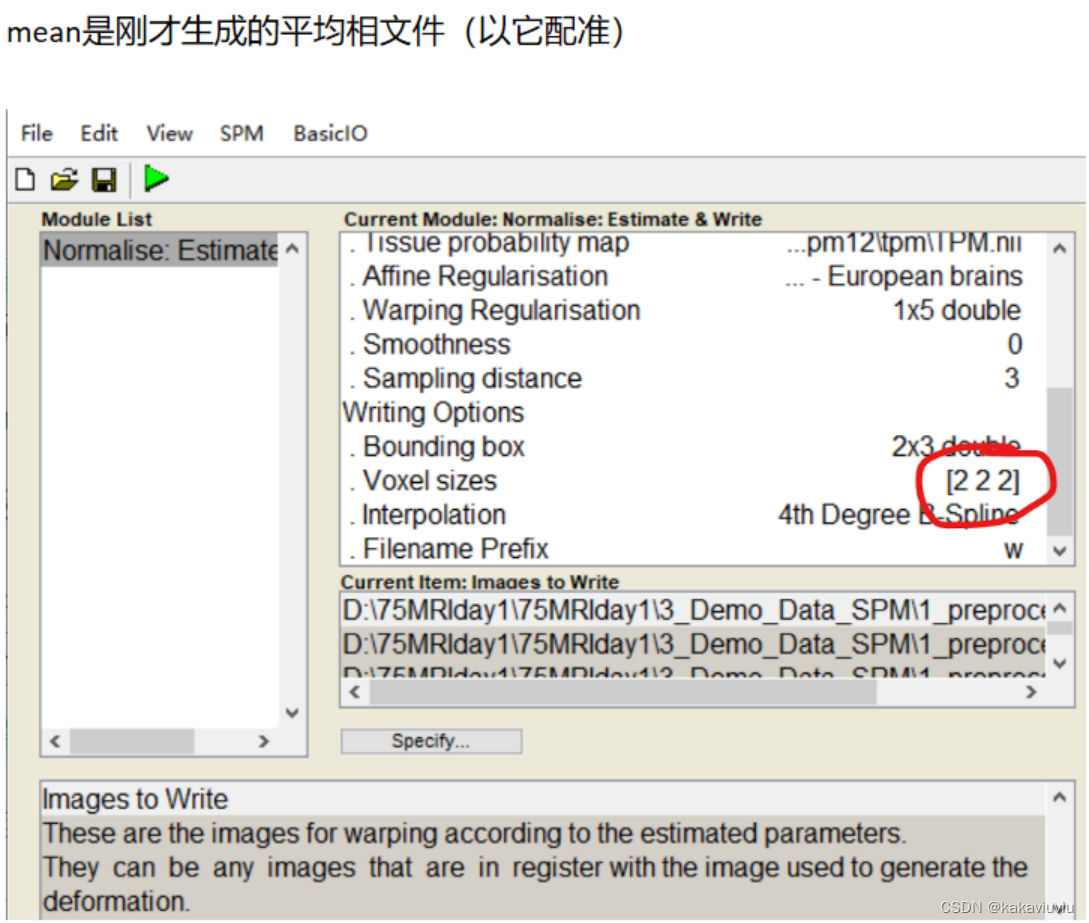

3.个体fMRI---应用第二步的形变场--->标准空间fMRI(Normaliz&Write)

再选择normalise

点dependency

修改boundingbox和体素3 3 3

Run

生成wra开头的文件